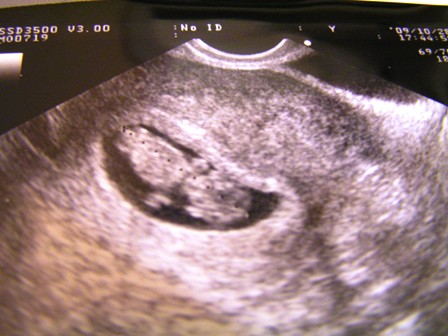

Minden okés odabent és kész!!!Mennek a drukkok a hétfői Uh-hoz...Én is voltam itt kint a barinőmmel, mikor ő volt babás, tök izgi volt